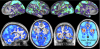

Resting-state functional magnetic resonance imaging has become a powerful tool for the study of functional networks in the brain. Even "at rest," the brain's different functional networks spontaneously fluctuate in their activity level; each network's spatial extent can therefore be mapped by finding temporal correlations between its different subregions. Current correlation-based approaches measure the average functional connectivity between regions, but this average is less meaningful for regions that are part of multiple networks; one ideally wants a network model that explicitly allows overlap, for example, allowing a region's activity pattern to reflect one network's activity some of the time, and another network's activity at other times. However, even those approaches that do allow overlap have often maximized mutual spatial independence, which may be suboptimal if distinct networks have significant overlap. In this work, we identify functionally distinct networks by virtue of their temporal independence, taking advantage of the additional temporal richness available via improvements in functional magnetic resonance imaging sampling rate. We identify multiple "temporal functional modes," including several that subdivide the default-mode network (and the regions anticorrelated with it) into several functionally distinct, spatially overlapping, networks, each with its own pattern of correlations and anticorrelations. These functionally distinct modes of spontaneous brain activity are, in general, quite different from resting-state networks previously reported, and may have greater biological interpretability.